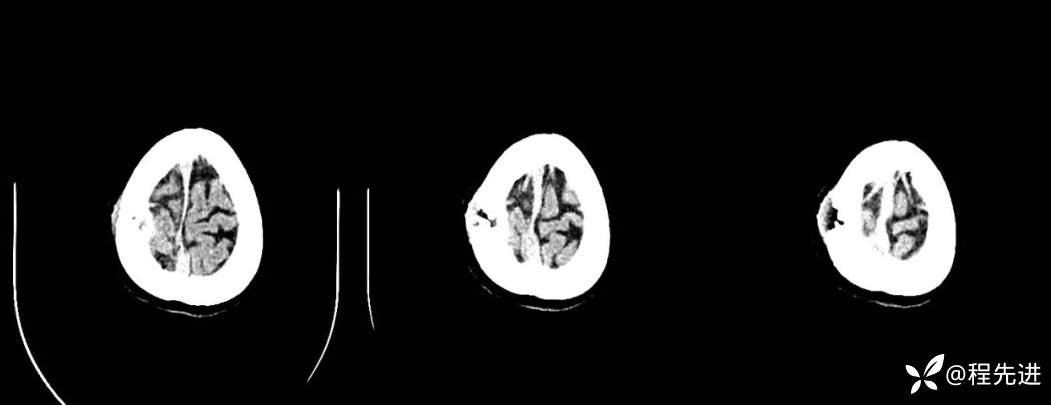

【现病史及既往史】:体检发现胰尾部肿块4年,当时手术病理提示异常增生性病变,现发现右侧顶部包块,逐渐增大,无明显感觉不适

查体:右侧顶部皮下可触及一包块,长约23mm,压痛(+),波动感(+-),可推动,边界清晰。

影像检查: